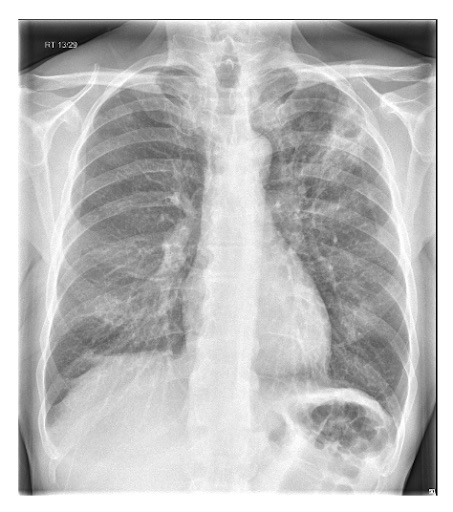

Considere uma tomografia computadorizada (TC) de tórax se a radiografia for de baixa qualidade ou se houver uma consolidação mal definida.[1]

Considere uma tomografia computadorizada de tórax ou outras investigações de imagem para pneumonia “complicada” ou alterações atípicas em uma radiografia torácica, como cavitação, padrão de consolidação multifocal ou derrame pleural.[89][Figure caption and citation for the preceding image starts]: Radiografia de tórax mostrando pneumonia cavitando no lobo superior esquerdoDa coleção do Dr. Jonathan Bennett. Usado com permissão [Citation ends].